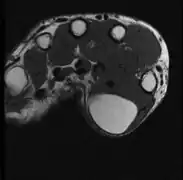

A physical exam is typically the easiest way to diagnose it. Rarely, a tissue biopsy or imaging may be required. The imaging modality of choice is magnetic resonance imaging (MRI) because it has superior sensitivity of distinguishing it from liposarcoma as well as mapping the surrounding anatomy.[22]

-

X-ray of a lipoma -

MRI showing lipoma of the arm -